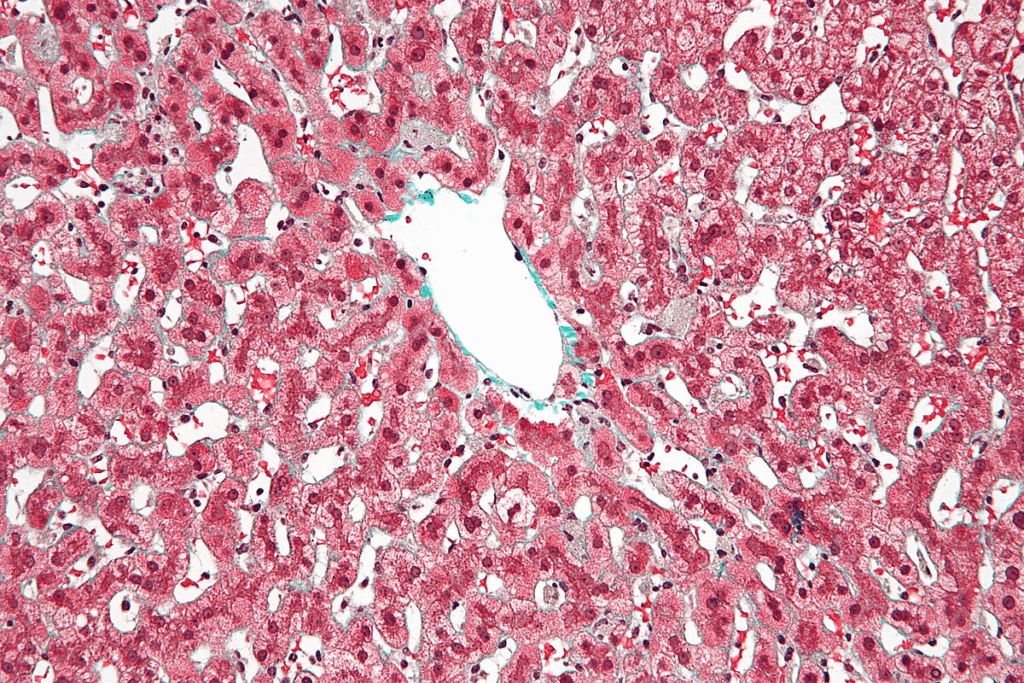

The liver sits in the upper right of the belly. It has four lobes: right, left, caudate, and quadrate. Hepatocytes, the main liver cells, handle detoxification and metabolism.

Liver lobules are its working parts. They have hepatocytes around a central vein. The liver gets blood from the hepatic artery and portal vein. This setup helps it filter toxins and make digestive enzymes.

Cellular Mechanisms of Regeneration

The liver’s ability to heal comes from its special cells and how they work together. Hepatocytes, the liver’s main cells, are vital in this healing process.

The healing starts with hepatocytes getting active and growing to replace the lost liver. This growth is guided by a network of signals that help cells work together.

The Role of Hepatocytes in Regeneration

Hepatocytes are the liver’s main workers. They grow fast to fix the liver’s size and function when it’s damaged. Their ability to grow back is what makes the liver heal from injuries or surgery.